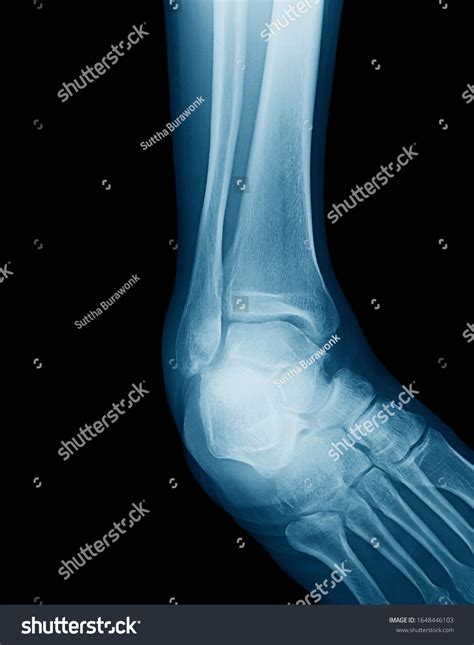

• Standard Radiographs (X-rays): Usually taken in three views (AP, Lateral, and Mortise view) to visualize bone alignment.

• Mortise View X-ray: A specialized projection that requires internal rotation of the foot to clearly see the joint space between the talus and the malleoli.

Another clinical concern is the widening of the mortise due to chronic ligament laxity. When the ligaments (specifically the syndesmotic ones) become stretched or torn, the fibula and tibia begin to move apart. This is clinically observed using an X-ray stress test, where a doctor evaluates whether the talus shifts within the mortise.